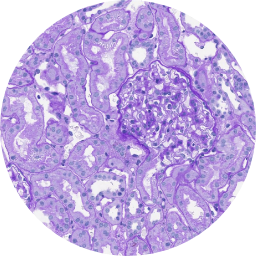

Welche Nierenkrankheit erkennen Sie auf dieser Biopsieaufnahme?

Lösung anzeigen Lösung verbergenC3-Glomerulopathie

Die C3G ist eine seltene, komplementvermittelte und chronisch-progrediente Nierenkrankheit.1,2

Aufgrund der eher unspezifischen initialen Symptome ist bei einem Verdacht auf eine C3G eine Nierenbiopsie mit anschließender Immunhistochemie unerlässlich für eine rechtzeitige und gesicherte Diagnose.3